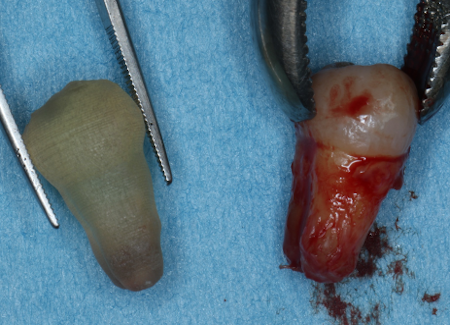

| STEP1 ドナー歯の抜歯 | STEP2 歯の移植及び縫合にて固定 |

|---|---|

![]() |